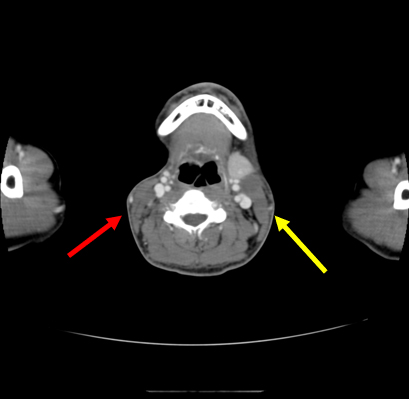

【画像所見まとめ】

• 右頸部に多発する嚢胞性(または壊死性)病変、リンパ節腫大

【その後の経過】

右頸部リンパ節、膿瘍、脾結節は縮小(抗菌薬なし)

新たに左頸部にリンパ節腫大出現膿瘍壊死のみ